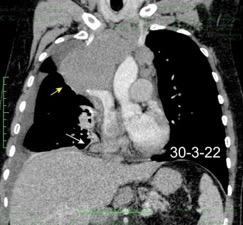

Marzo 2014: Perforación longitudinal distal secundaria a episodio de vómito (síndrome de Boerhaave). Derrame pleural izdo. que evoluciona a empiema.

Wang C-T et al. Tension hydropneumothorax in a Boerhaave syndrome patient: A case report . World J Emerg Med, 2021. Katabathina V et al. Nonvascular, nontraumatic mediastinal emergencies in adults:a comprehensive review of imaging findings. Radiographics. 2011.